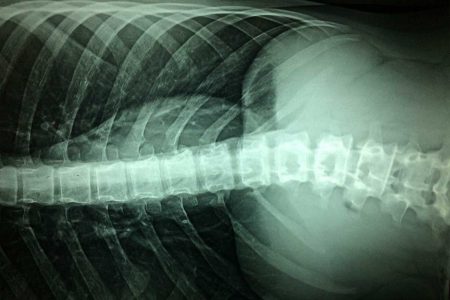

Bilim İnsanları, Zedelenen Omuriliği Hastaların Kök Hücreleriyle Onardı

Yale Üniversitesi ve Japonya’da çalışan araştırmacıların 18 Şubat’ta Journal of Clinical Neurology and Neurosurgery bülteninde aktardıklarına göre, omurilik zedelenmelerine sahip hastaların kemik iliğinden çıkarılan kök hücrelerin (MSC) damar içine enjekte edilmesi, motor fonksiyonlarda kayda değer iyileşmelere yol açmış.